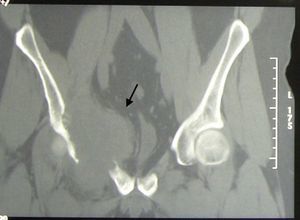

A 43-year-old male came to the clinic due to mechanical lower back pain, which had lasted for 2years. Physical examination showed painful limitation for right leg flexion and extension, with no neurological deficit. Laboratory analysis highlighted hemoglobin 10.6g/dl, normal ESR and GGT 111U/L (0–40). Simple X-ray (Fig. 1), CT (Fig. 2) and MR (Fig. 3) of the hips evidenced a 90mm×80mm×80mm mass in the right hemipelvis with an osteolytic component which affected half of the cotillus, iliac and pubic ramus, displacing the bladder and subjacent structures leftward.

X-ray findings reflect osteolysis, erosions, periostitis and soft tissue masses, as in our case. Immunohistochemistry is important to establish the differential diagnosis.5